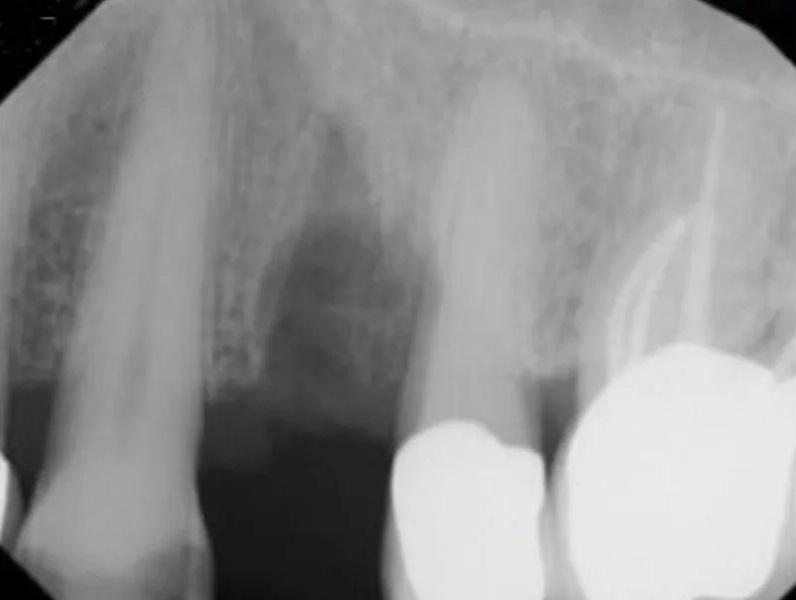

Пациент мужского пола 68 лет был направлен эндодонтистом с диагнозом симптоматический необратимый пульпит с нормальными периапикальными тканями и значительной потерей костной ткани с вовлечением фуркации у первого премоляра верхней челюсти слева (зуб № 2.4). Из-за состояния пародонта была показана реабилитация с помощью имплантационной реставрации. Конусно-лучевая компьютерная томография (КЛКТ) выявила потерю кости с дистальной стороны пораженного зуба, размером 5 мм в ширину и 9 мм в длину соответственно, с вовлечением альвеолярного костного гребня (Фото 1 – Фото 4).

Фото 4. Предоперационный сагиттальный срез КЛКТ первого премоляра верхней челюсти слева, демонстрирующий область рентгенопрозрачности, вовлекающую более двух третей корня, включая пришеечную область и альвеолярный костный гребень.